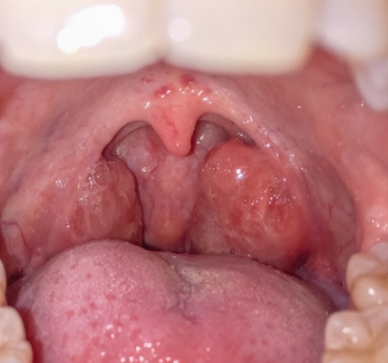

Frequent tonsillitis refers to repeated episodes of inflamed tonsils causing sore throat, fever, and difficulty swallowing. While an occasional episode is common, recurrent tonsillitis can significantly affect work, sleep, and quality of life.

As an ENT specialist, I often see adults who keep taking antibiotics several times a year without lasting relief. In such cases, repeated infection may indicate chronic tonsillar disease, where specialist assessment is necessary to prevent complications and guide long-term management.

3. Tonsil Stones (Tonsilloliths)

Debris trapped in tonsils causes inflammation and odour.

- Evaluation for tonsil stones